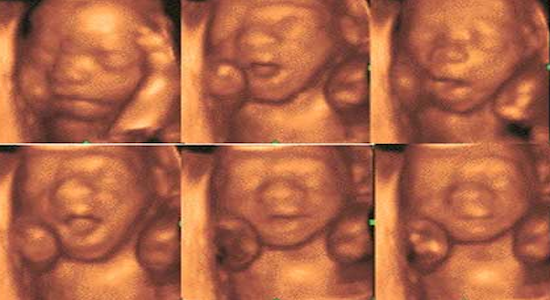

Echographie 3D, souvenir, plaisir, ludique ou encore affective, les dénominations sont nombreuses mais la pratique reste la même : une échographie pratiquée par un professionnel non médecin pour que les parents puissent conserver des photos et un dvd de souvenir de leur enfant dans les premières mois de sa vie. Bien que plébiscitée par les parents, le corps médical s’inquiète de cette pratique que l’Agence nationale de sécurité du médicament (ANSM) déconseille depuis 2005. En décembre dernier, le Collège des gynécologues et obstétriciens français dénonce une exposition inutile sinon risquée des fœtus aux ultrasons et réclamé l’application du principe de précaution en réservant la pratique des échographies aux seuls médecins et sages-femmes. En réponse, le gouvernement d’alors saisit la Haute autorité de santé (HAS) et l’Agence nationale de sécurité du médicament sur ces échographies fœtales à visée non médicale. Le rapport de la HAS rendu public hier porte un nouveau coup à une activité déjà sur le déclin depuis cet hiver. Elle précise que l’échographe est un dispositif médical qui doit, à ce titre, n’être utilisé qu’à des fins médicales et par des professionnels de santé.

L’ANSM, qui doit se pencher sur l’évaluation des risques pour le fœtus, n’a pas encore rendu son rapport. Mais certains spécialistes s’inquiètent des effets potentiels d’une application prolongée de la sonde de l’échographe sur les zones fragiles qui intéressent particulièrement les parents : le visage et les organes génitaux du fœtus. L’effet thermique des ultrasons est démontré et il n’est pas exclu qu’une exposition prolongée entraîne une augmentation de température dommageable pour l’enfant à naître. Les gynécologues-obstétriciens préconisent donc, par prudence, de s’en tenir aux échographies médicalement justifiées.